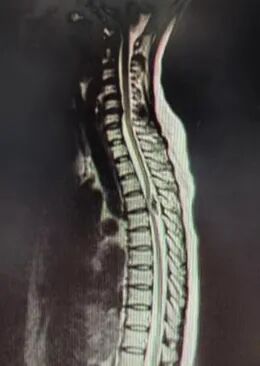

入院后,医生详细查体及询问病史后判断:患者目前症状应考虑多种原因引起,腰椎疾病无法解释目前症状,应考虑胸椎管上段病变。后经胸椎MRI检查诊断为:胸椎管占位肿瘤病变(T4-5)。CT提示占位病变考虑脊膜瘤并骨化可能性大。

磁共振可以看到肿物位于脊髓后方,椎管狭窄,脊髓严重受压